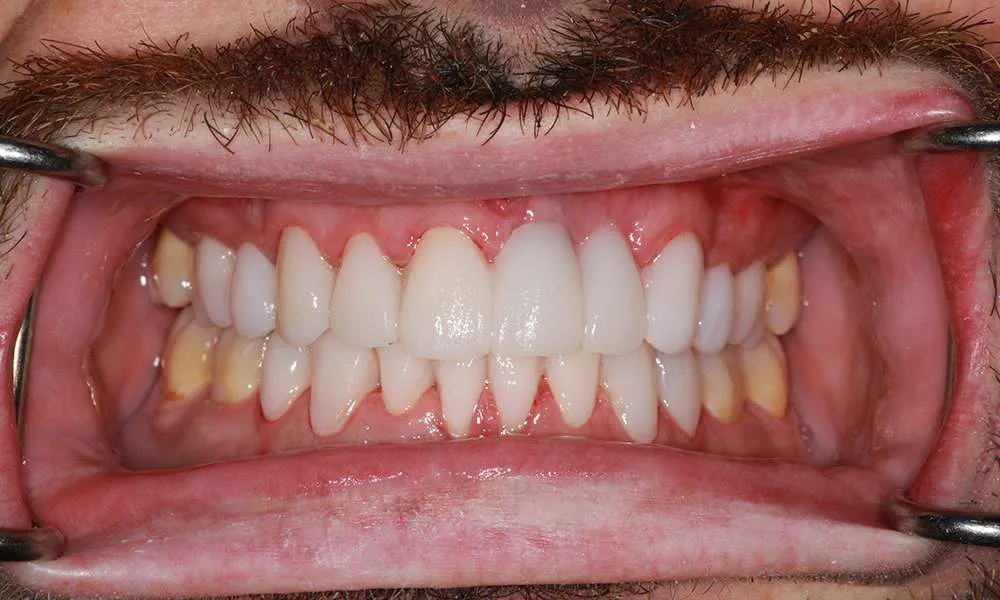

Real Stories, Real Results: Case Studies Showcasing How Our Personalized Approach Transforms Smiles and Lives

Complex Cases

Witness the Remarkable Changes We Can Achieve